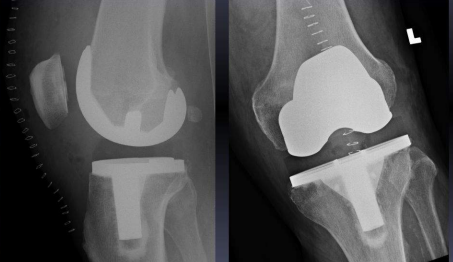

Complications that can occur following a knee replacement can include knee stiffness, periprosthetic fractures (Fig 2), prosthetic joint infection, aseptic loosing, patellar mal-tracking and heterotrophic ossification with joint infection or bacteremia being an absolute contraindication for the procedure. The designs of implants used for total knee replacement can vary from unconstrained or cruciate retaining to partially constrained implants to fully constrained implants [5].

Cruciate retaining type of implants (fig 3) were used for all patients selected for the study and medial Parapatellar approach to knee (Fig 4) used in all cases. For closure Number 2 vicryl for the capsule and subcutaneous tissue and staples used for skin. Post-operative mobilization was started on post op day 2.

Figure 3